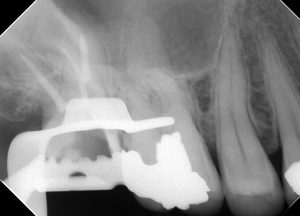

MB根が開かないというケース。

これ、湾曲がめっちゃ強いケースで、歯医者はみんな嫌がります。

こんなに曲がっていると、

途中でファイルが引っかかり、ステップが出来てしまう。

こんな時は『ハイフレックス』が超便利!!

このケース、難しいのが実は湾曲と関係なくて、

なんと、石灰化がひどくて、CTを撮りました

全然入口がわからなくなっており、CT上でも消えてました( 一一)

あと2mm頑張れば根が見えるというのがCTでわかっていたのでそーっと削りました・・・